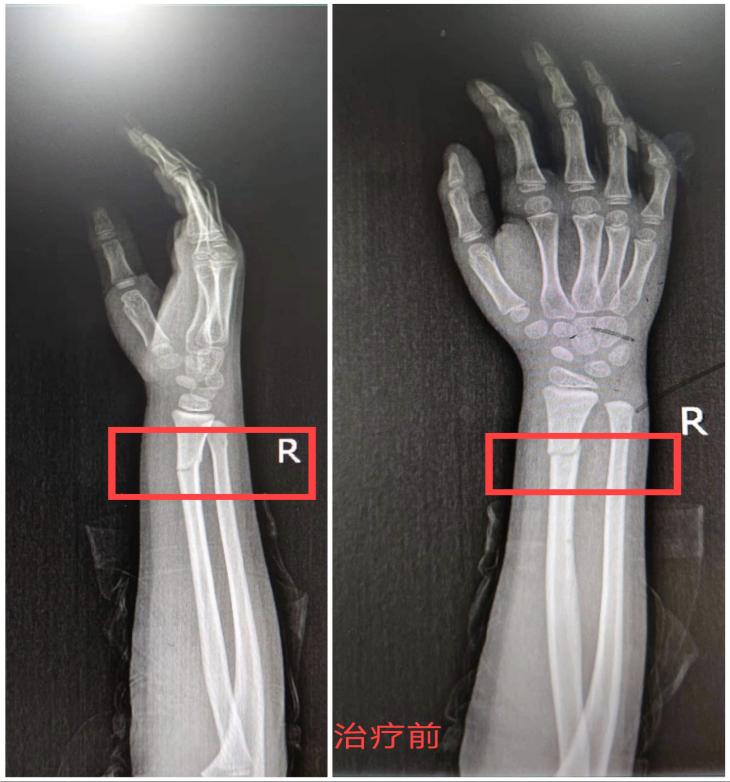

检查完了左边,他接着以同样的方式开始检查孩子右侧,当检查到孩子右手腕上5厘米的位置时,孩子开始说疼了,刘医生对比了左边的手腕后发现,左边确实比右边要肿一些,心里顿时觉得不妙。他跟孩子妈妈说:“应该是这里骨折了,需要拍个片子确定一下。不过您不用担心,即使是骨折也是不严重的那种,不需要做手术。放心吧!”

x线检查的结果显示孩子确实是骨折了,还有轻微的移位。当得知孩子的确是骨折之后孩子的妈妈又开始变得焦虑不安,紧张地问刘医生:“大夫,孩子的手会不会受到影响?这个骨头能不能自己长好啊?”刘医生告诉孩子的妈妈,孩子的骨头愈合能力特别强,只要把移位的地方对好,之后骨头就能慢慢愈合,对手的功能也不会有任何影响。然后,耐心向孩子妈妈讲解了治疗方案,征得孩子妈妈同意后,在孩子骨折的部位打上了石膏,固定好之后又拍了个片子看看复位的效果。